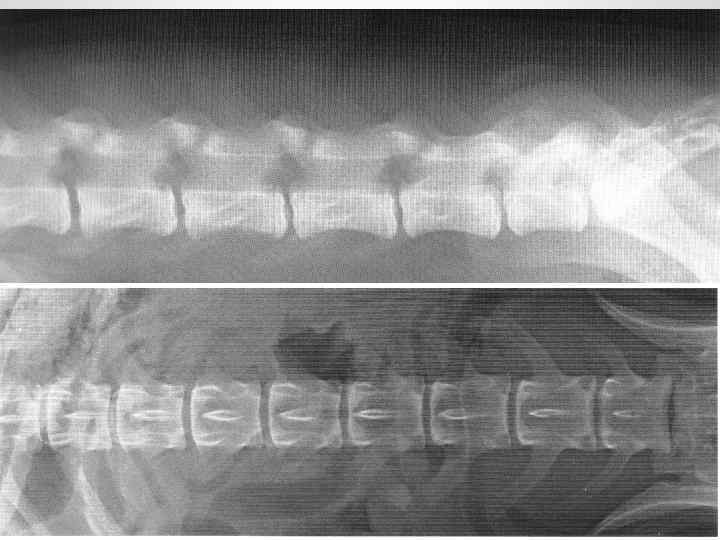

Рентгеноанатомия

МГАВМи. Б им. К. И. Скрябина

Макропрепарат поясничного отдела позвоночного столба МГАВМи. Б им. К. И. Скрябина